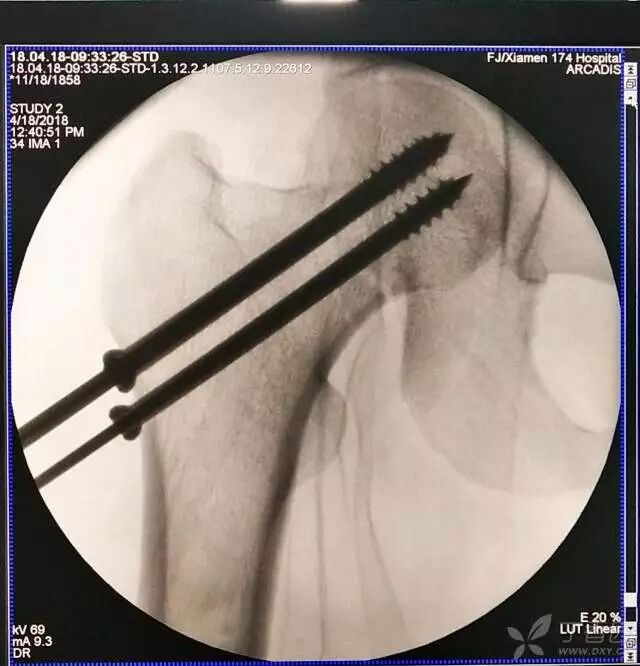

6. 然后依次打入倒品字上方的两枚导针

牵引床怎么用视频详解:如何不使用牵引床做好一台股骨颈骨折?_https://www.jmylbn.com_新闻资讯_第14张